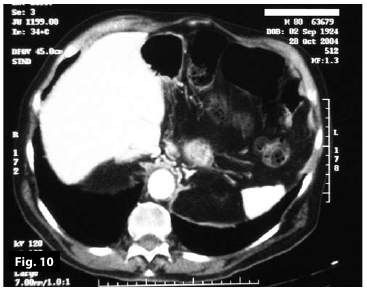

Figure9

Figure10

Figure9-10